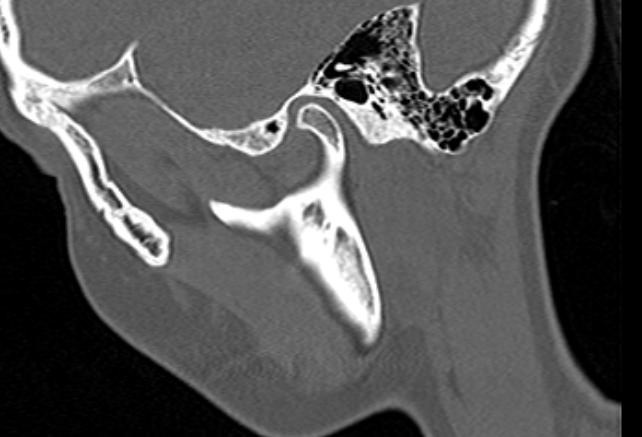

Наиболее точным и информативным методом диагностики костной патологии ВНЧС является мультиспиральная компьютерная томография. КТ относится к лучевым методам исследования, то есть для сканирования применяется рентгеновское излучение. В отличие от обычного рентгена томограф проводит одномоментно множество тончайших срезов исследуемой зоны, которые в дальнейшем проходят цифровую обработку. В результате получаются детальные снимки и трехмерные изображения области височно-нижнечелюстных суставов, которые позволяют проводить точную и достоверную диагностику.

Для оценки функции височно-нижнечелюстных суставов КТ-сканирование проводится в нескольких положениях: с открытым ртом и закрытым ртом. С помощью таких функциональных проб можно оценить положение суставной головки нижней челюсти при движениях нижней челюсти, выявить привычные вывихи и подвывихи суставов.

С помощью КТ можно оценить состояние костной ткани суставных головок нижней челюсти, внутрисуставного мениска, суставной капсулы, связочного аппарата и жевательных мышц.

- Дегенеративно-дистрофические заболевания (артроз височно-нижнечелюстных суставов, который проявляется уменьшением просвета внутрисуставной щели, истончением хрящевой ткани, разрастанием остеофитов);

- Субкортикальные кисты (полость, образующаяся на месте суставной головки нижней челюсти в результате резорбции (то есть разрушения) костной ткани;